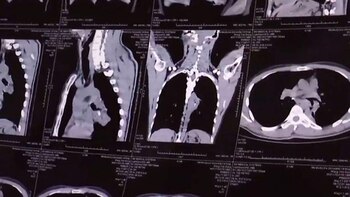

Pero hace algunas semanas, esos ataques de tos volvieron con sangre. Wang fue internado, le realizaron tomografías y los médicos descubrieron un extraño objeto alojado en sus pulmones.

Con una endoscopía lograron llegar al objeto, que resultó ser la tapa de un bolígrafo parcialmente disuelta. Wang recordó entonces que cuando era pequeño la había inhalado por accidente por su nariz. Pero luego se olvidó y nunca vinculó los episodios agudos de tos con aquel accidente.

El equipo médico del doctor Zhou Kangren quedó atónito cuando logró extraer el objeto que había estado alojado en los pulmones de Wang por cerca de 20 años.